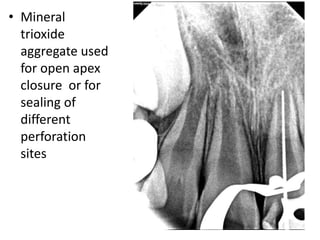

• Mineral

trioxide

aggregate used

for open apex

closure or for

sealing of

different

perforation

sites

• Mineral trioxide aggregate used foropen apex closure or for sealing of different perforation sites